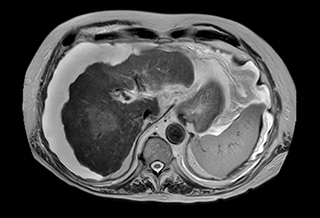

Free breathing abdominal MRI with VitalEye

Ascites can be hard to image, but excellent result is obtained with Ingenia Ambition. This high resolution image demonstrates the high quality that can be obtained with VitalEye and the patient just breathing normally. The acquisition time is fast thanks to the accuracy of the respiratory gating with VitalEye** and it also saves the time needed to put a respiratory belt on the patient.

MCVI VitalEye abdomen

3D T2 with VitalEye

MCVI VitalEye ascites